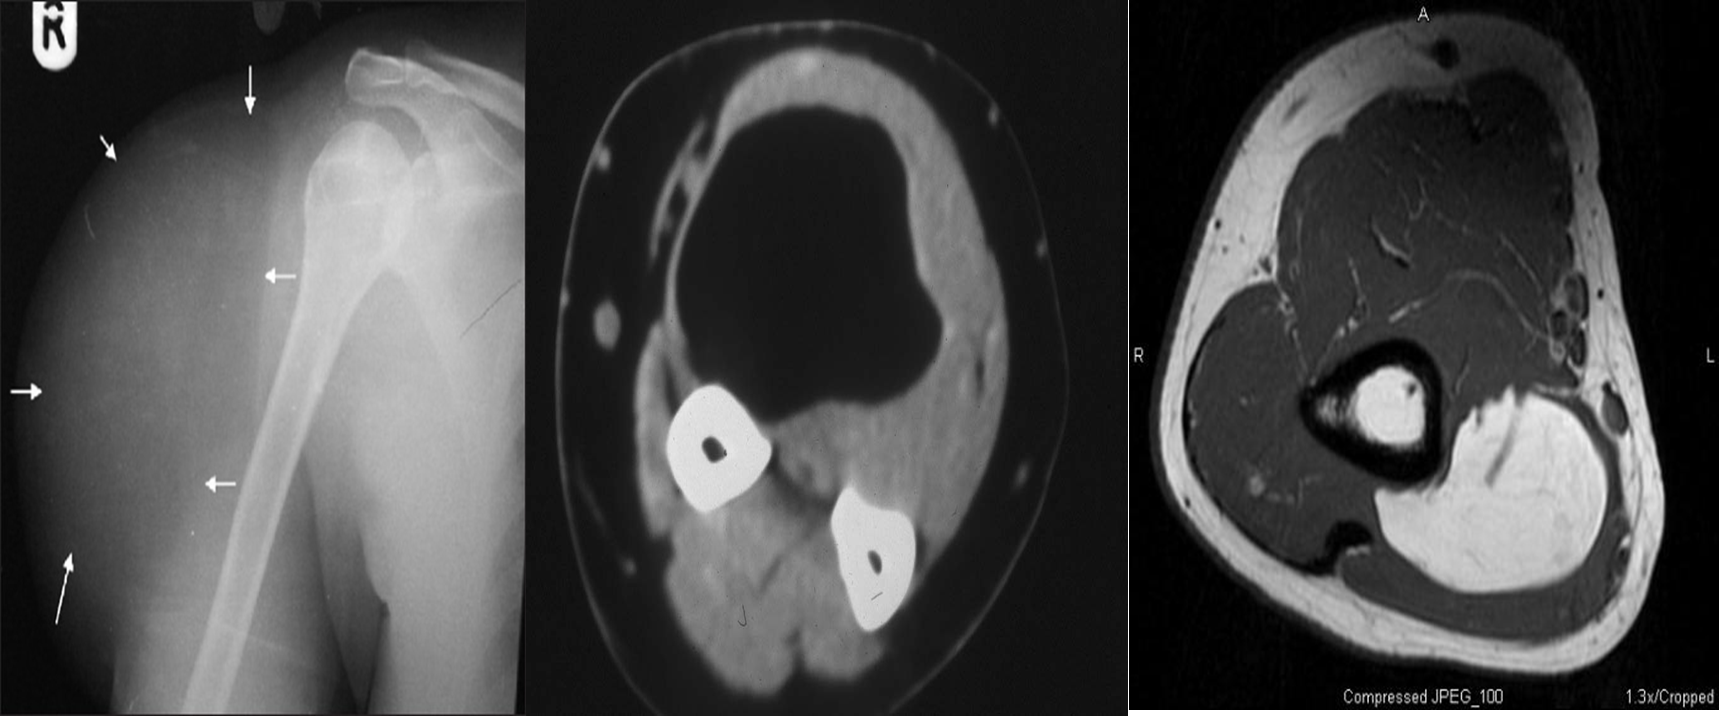

Soft tissue tumor right arm: LIPOMA

B- CT. Lipoma Fatty tissue appear dark on CT and so the tumor

C- MRI. Lipoma Fatty tumor give bright signal on MRI